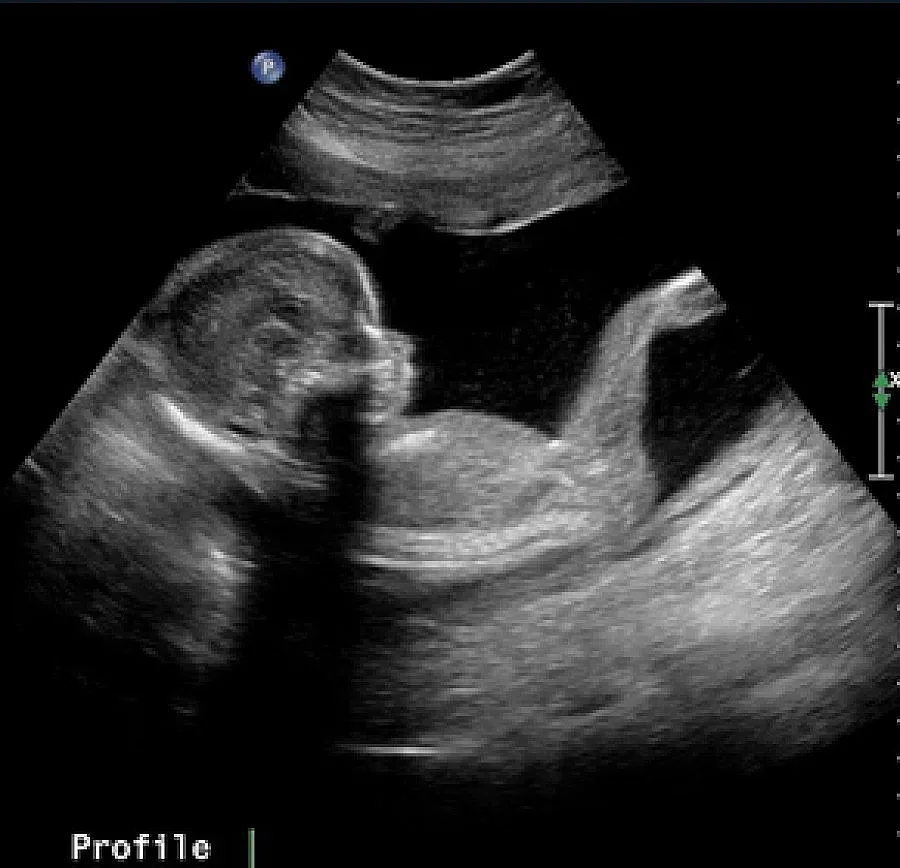

София. Приблизително 40 000 жени в Българи имат нужда от донорска яйцеклетка, за да станат майки. Те са на възраст между 25 и 45 години, но са със сериозни заболявания, заради които не могат да заченат със собствен генетичен материал, предаде БНР.

По думите на председателя на Фондация "Искам бебе" Радина Велчева, за да стане една жена донор трябва да е на възраст до 34 години и да е майка.

"Съществуват много митове, които витаят за донорството, един от тях е, че процедурата е много тежка и травмираща жената. Не се подлагат на силна хормонална стимулация, тъй като са здрави жени. След стимулация няма риск от изчерпване на яйчниковия резерв на жената донор. Пункцията на яйцеклетки не е операция. Тя е една манипулация, която трае за около две-три минути, с упойка е, жената не чувства нищо и буквално след 15 минути тя е на крака," обясни специалистът.

Велчева обясни, че над 100 жени са дарили яйцеклетки тази година в програмата "Искам бебе". В заключителния ден на седмицата, посветена на донорството в болница "Надежда", министърът на здравеопазването д-р Таня Андреева определи донорството като високохуманен акт за взаимопомощ.